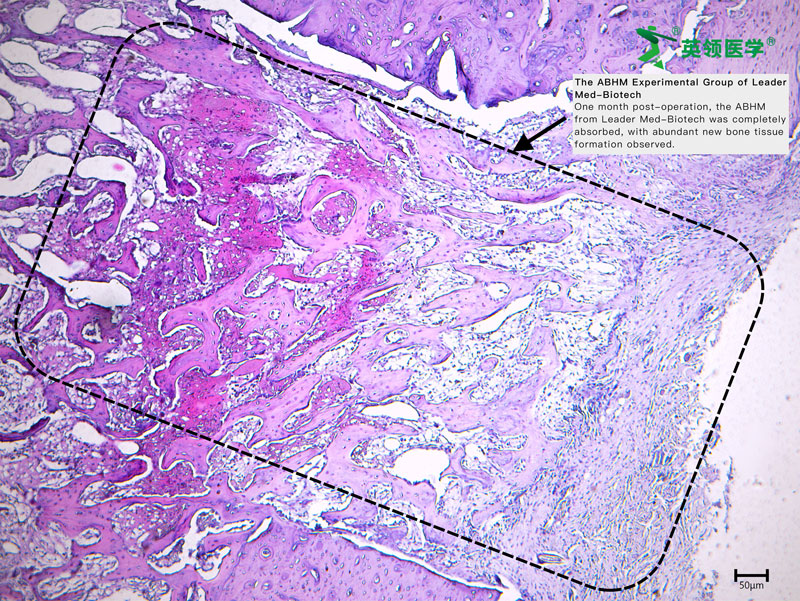

During the trial, ABHM demonstrated excellent clinical performance and safety. Its biodegradable properties and ease of use were highly praised by surgical experts from multiple clinical centers. The product rapidly achieves hemostasis by mechanically sealing bone wound surfaces, and it degrades completely within four weeks. This effectively avoids complications associated with traditional bone wax, such as impaired bone healing, foreign body granuloma, chronic inflammation, and infection—offering a safer and more physiologically compatible solution for bone wound management.